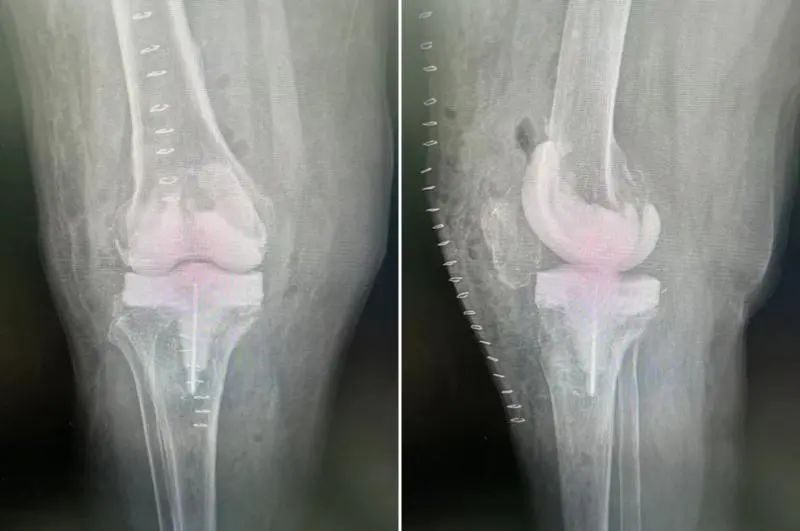

二期为患者行Spacer取出,翻修假体植入术

假体表面感染组织及髋关节Spacer植入术后平片